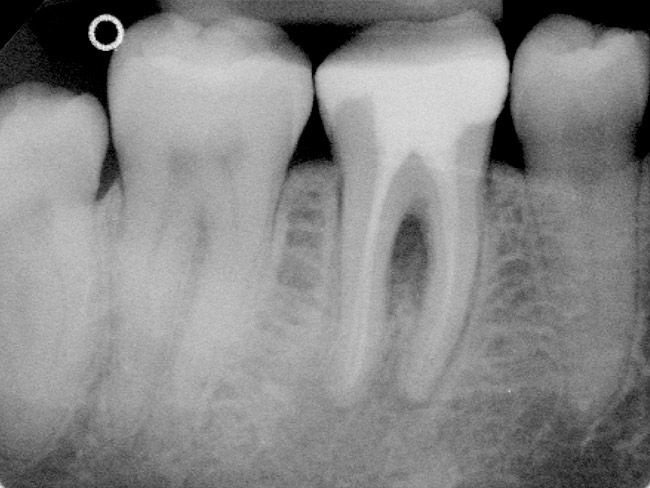

Figure 2a  Tooth No. 19 A new coronal restoration had been recently placed after root canal treatment. The patient was sensitive to biting and percussion. The preoperative radiograph revealed an apical pathology around the mesial and the distal roots.

Figure 2a

Figure 2b  The patient wanted to keep the new restoration intact. Osteotomy and root-end surgery were performed under a surgical microscope.

Figure 2b